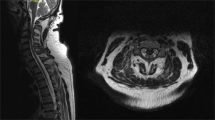

This paper presents the results of a study on the pathological changes associated with post traumatic central spinal cord necrosis.

Yeo, J., Stabback, S. & McKenzie, B. Central necrosis following contusion to the sheep's spinal cord. Spinal Cord 14, 276–285 (1977). https://doi.org/10.1038/sc.1976.45